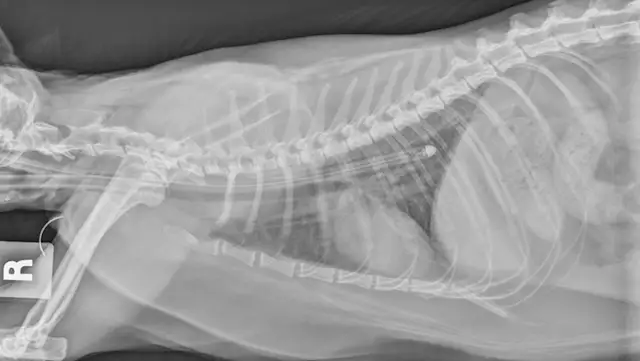

Esophagostomy tubes (E-tubes; Figure 2) are commonly used in patients with feline hepatic lipidosis. Placement requires a stable patient with corrected electrolyte abnormalities, normal cardiovascular status, and tolerance of brief general anesthesia. In the author’s experience, patients are stable for anesthesia and E-tube placement 12 to 24 hours after admission with appropriate hospitalization, treatment, and supportive care. For unstable patients, nasoesophageal or nasogastric tube placement can be considered, as these tubes are often placed without anesthesia. In the author’s experience, E-tubes allow the clinician to provide a more suitable, nonliquid diet (liquid diets often result in diarrhea) with fewer complications than with gastrostomy tubes; they also ease long-term at-home management, as owners can use the E-tube for continued enteral feeding following discharge. After the E-tube is placed, a radiograph should be obtained to ensure appropriate positioning, typically between the seventh and ninth intercostal spaces (Figure 3). Placement in the proximal esophagus may result in tube migration; placement in the stomach may result in esophageal reflux, nausea, discomfort, and vomiting.  E-tubes can remain in place as long as needed (in author’s experience, typically 3-8 weeks).